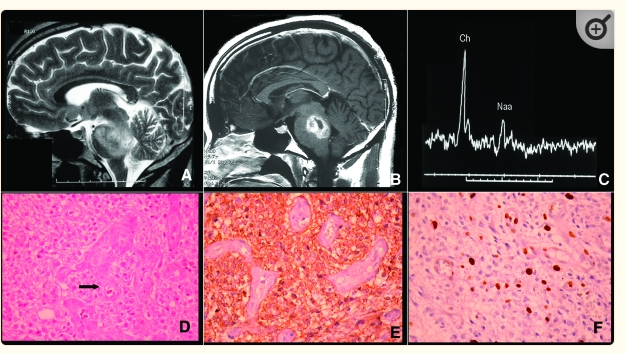

Hình 4: U vùng thân não: Oligoastrocytoma-grade II

Hình 5: U vùng cầu não: Anaplastic oligodendroglioma Grade III